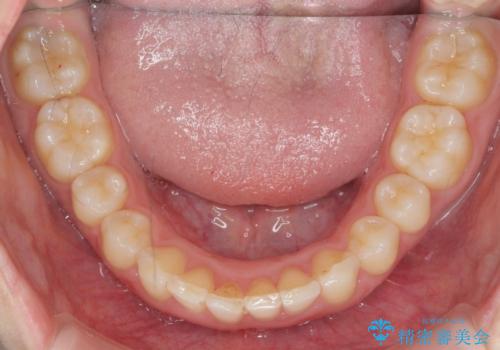

前歯のがたつき 深い噛み合わせを改善したい

- 「前歯のガタつきをきれいにしたい、噛んだ時に下の前歯が見えないことを改善したい」とマウスピース矯正を希望され来院されました。

マウスピースに加え、矯正用マイクロインプラントやゴムを併用し、がたつきや噛み合わせの深さを改善していきます。

ゴムかけやマウスピースの装用時間、しっかりとマウスピースをはめ込むチューウィーをしっかりと使用したことで良好な治療結果を得ることができました。